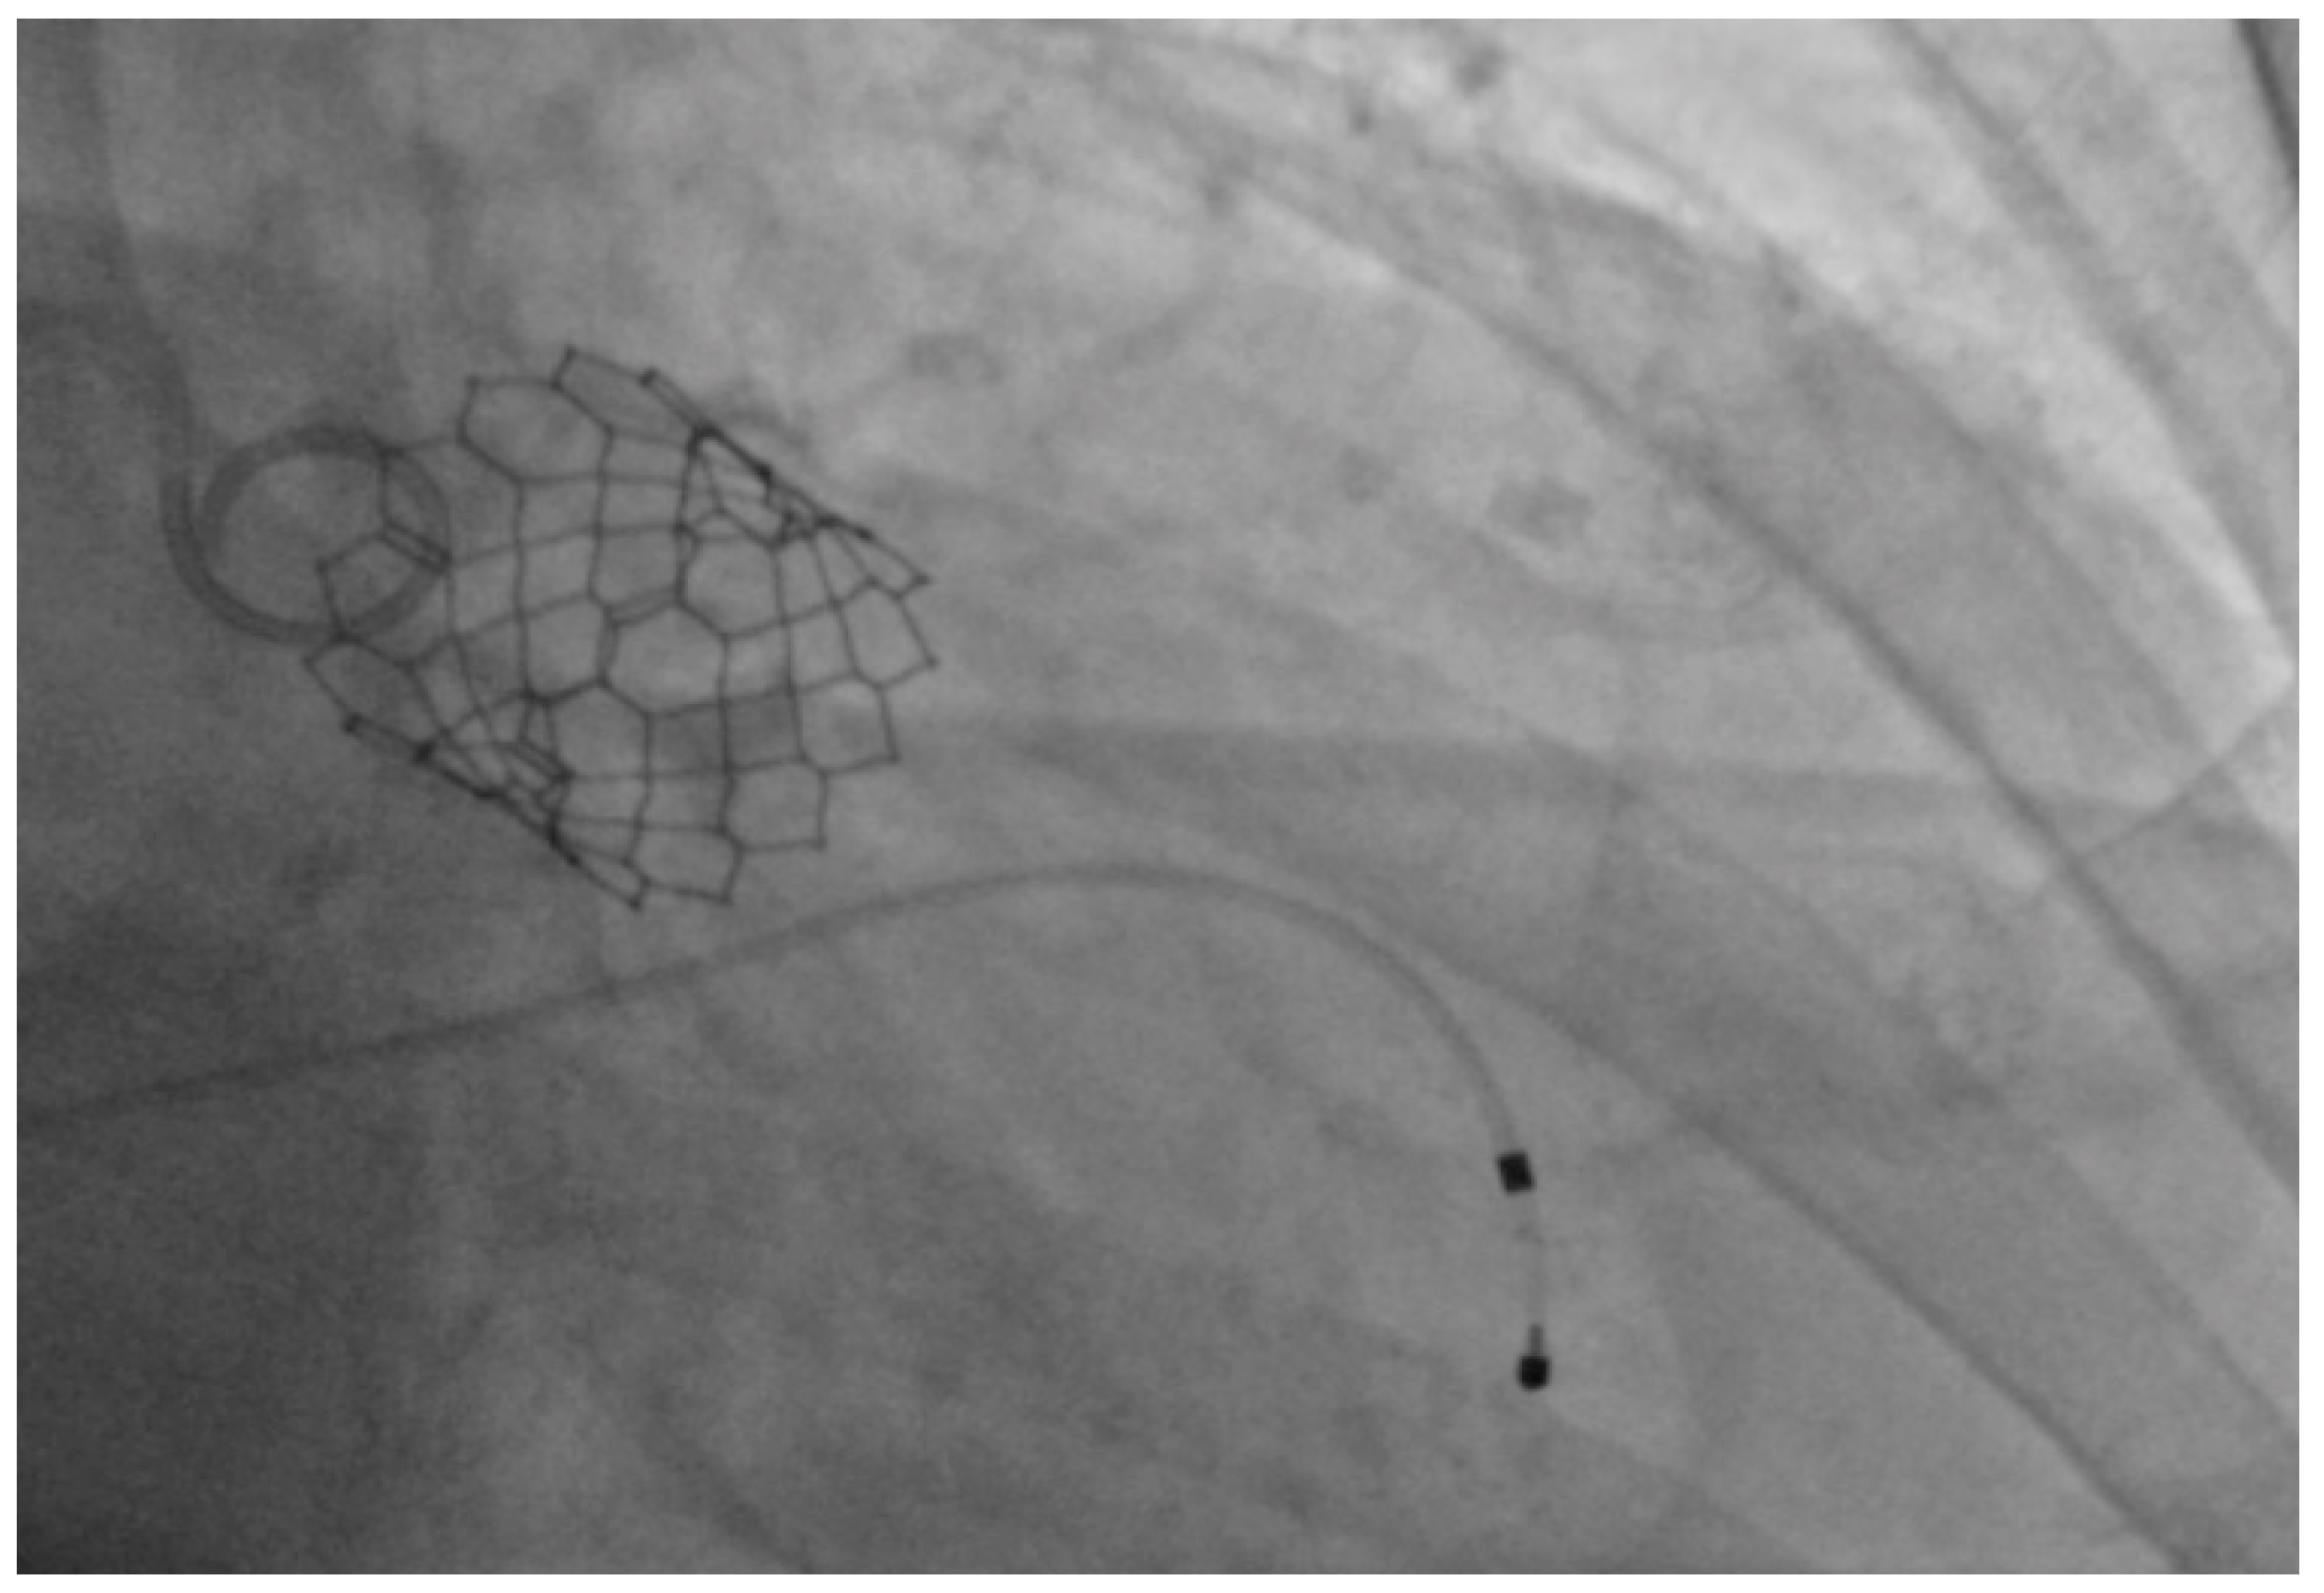

Under general anesthesia, the right and left femoral arteries were each accessed with 6-french sheaths. A temporary pacemaker was placed in the right ventricle through an 8-french sheath in the right femoral vein. Balloon valvuloplasty was performed by advancing a balloon via the right femoral artery sheath, and during rapid ventricular pacing at 160 beats per minute, inflating it across the aortic valve to clear the stenosis and to deploy the 26-mm SAPIEN S3 bioprosthetic aortic valve (Figure 1), which expanded within the native aortic valve (Figure 2). The purpose of rapid ventricular pacing during TAVI is to reduce cardiac output, which facilitates balloon inflation across the valve and placement of the bioprosthetic aortic valve. The mean valvular gradient after TAVI decreased to 1.9 mm Hg (normal is <5 mm Hg). There were no intraoperative complications. The patient was extubated and transferred to the coronary care unit with the temporary transvenous pacemaker, which was removed two days later.

Figure 2.

Expanded SAPIEN S3 valve within the native aortic valve.